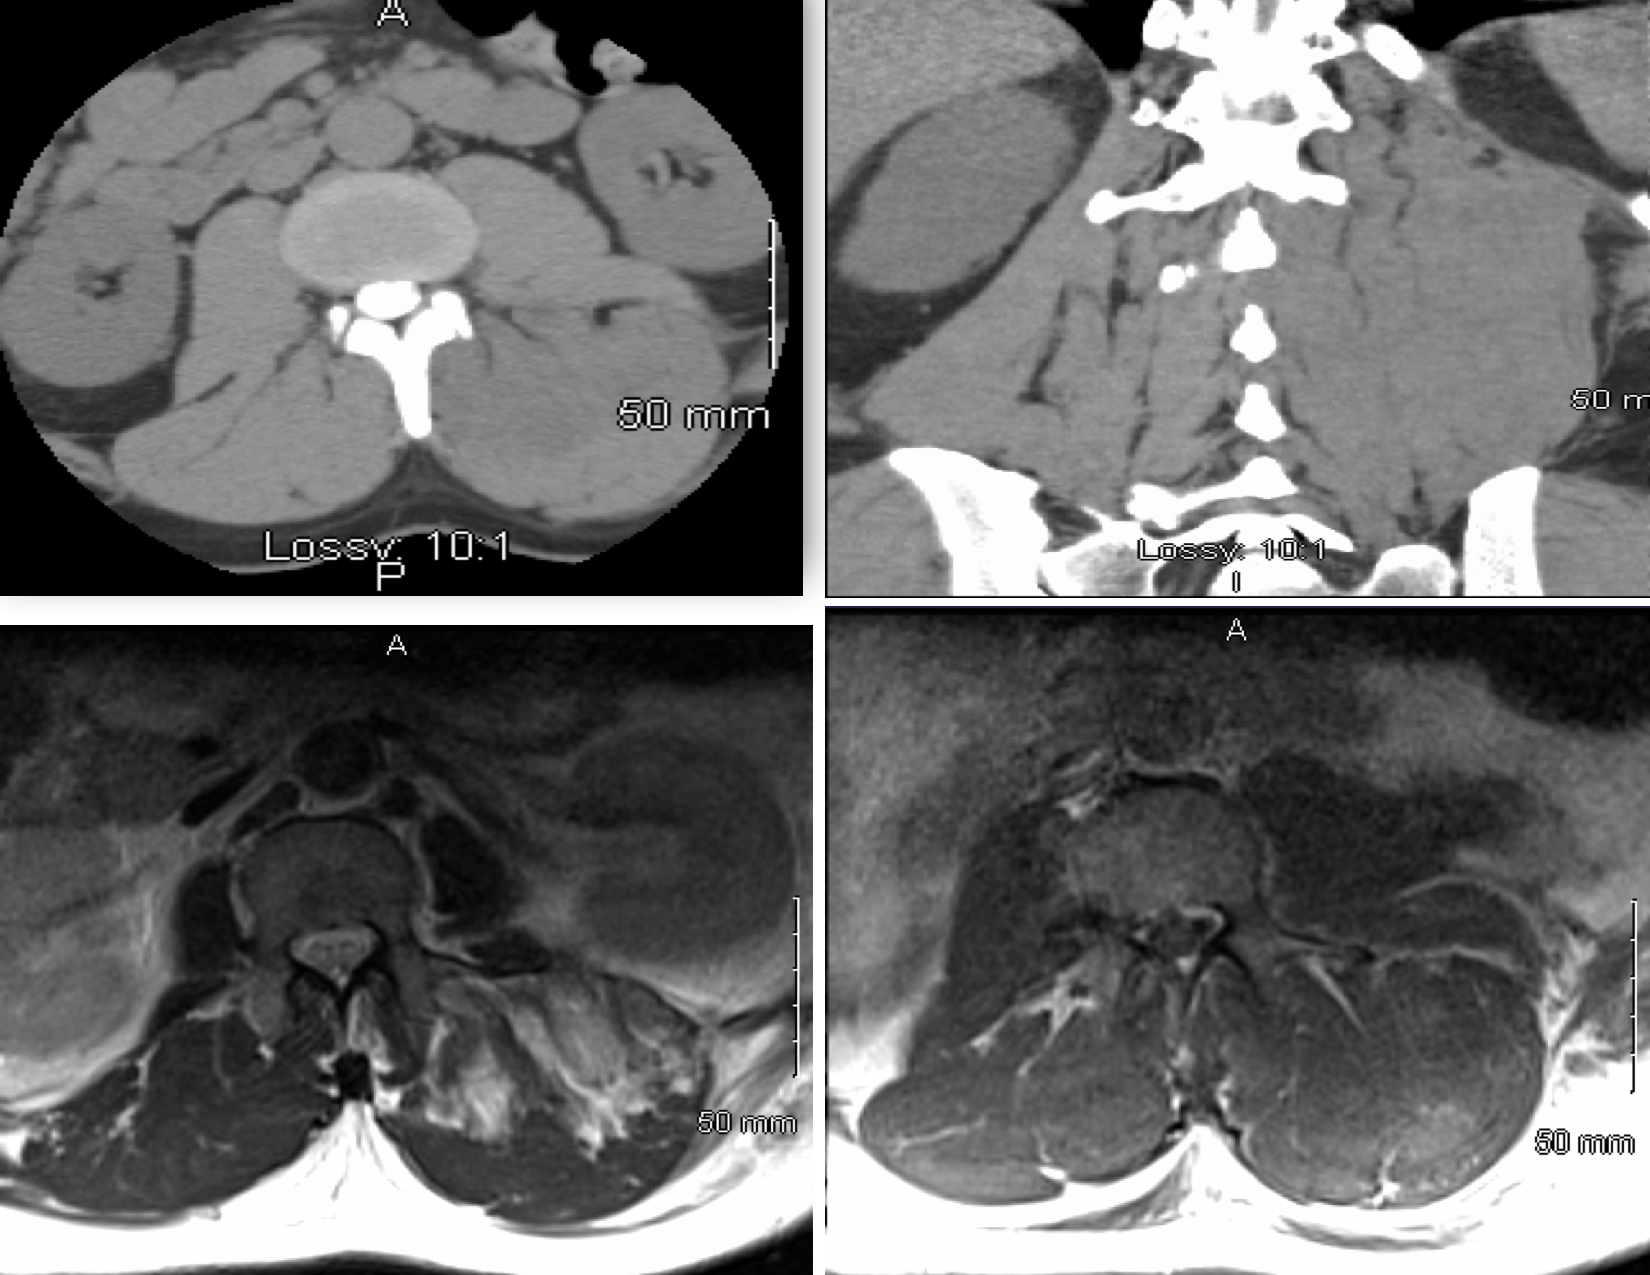

Computed tomography demonstrates the edema of the muscles of the Gluteal Compartment Syndrome gluteal compartment syndrome is an orthopaedic emergency that may be more prevalent and associated with higher morbidity and mortality than previously recognized. gluteal compartment syndrome. The gluteal region is a rare. gluteal compartment syndrome (gcs) is a rare surgical emergency where ischemic changes occur to the gluteal muscles. compartment syndrome, an exceptionally rare condition, is a. Gluteal Compartment Syndrome.